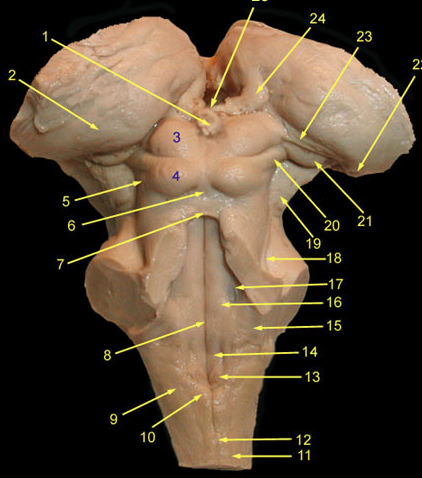

optic nerve

A lesion of the right optic nerve causes

optic chiasm

(note proximity to infundibulum and hypothalamus)

X - loss of vision in the temporal half of both visual fields:

bitemporal hemianopsia3

optic tract

thalamus and the crus cerebri

A lesion of the right optic tract causes a complete loss of vision in the left hemifield:

contralateral “homonymous” hemianopsia.

prectum

superior colliculis

occulomotor

occulomotor nerve

lateral geniculate n.